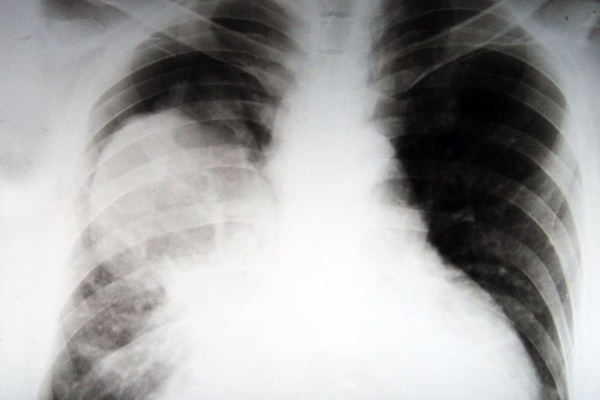

Статистические данные исследований говорят о том, что именно курение становится причиной развития рака бронхолегочной системы. И связано это в большей степени с канцерогенами сигарет: попадая в организм постоянно и в больших количествах, накапливаясь там, химические соединения дыма и продуктов сгорания приводят сначала к нарушениям работы слизистой бронхов, их эпителиального слоя и железистой ткани. Затем развиваются хронические нарушения процессов клеточного образования и кровоснабжения, а далее начинаются процессы деформации клеток, замещения нормального цилиндрического эпителия плоским многослойным, патологических изменений железистой ткани. Это приводит к образованию плоскоклеточного рака (слизистая рта и гортани) и аденокарциномы (рак легких).

В 90% случаев установленного рака легких выясняется, что пациенты онкологической пульмонологии — курильщики. Это явно указывает на курение, как на одну из самых значительных причин возникновения ракового заболевания. А уж в условиях современной экологической обстановки курение становится настоящей атомной бомбой, запускающей процессы развития рака. Выхлопы автомобилей и выбросы промышленных предприятий, электромагнитное и радиационное излучение, пыль, бактерии и вирусы, различные заболевания бронхолегочной системы (например, заболеваемость астмой и ХОБЛ растет год от года) — на этом фоне курение становится терминальным фактором-провокатором рака.

По данным медицинской статистики, в городах раком легкого заболевают примерно 12,7% мужского населения, там бронхогенный рак выходит на 3-4 место по частоте заболеваемости. В крупных же городах с развитой промышленностью частота выявления рака составляет 18% — это уже первое место в общей структуре онкопатологий. Оценивая данные статистики, нужно также помнить, что примерно 30% случаев рака легких и смерти от него остаются не выявленными, человек считает, что болен тяжелой астмой, туберкулезом, их же указывают в причинах смерти.